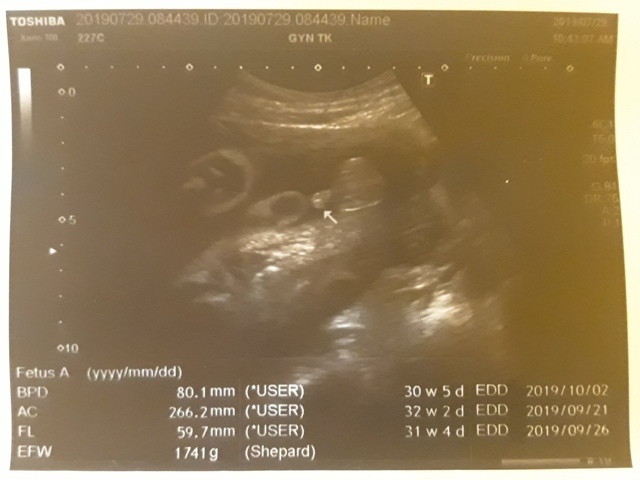

| 仙人掌(2019/07/29)的真心話 星期一 天氣晴 編號19-199 |

近八次產檢資料統計↓

| 2019年07月29日 | 80.1mm (8%) | 266.2mm (10%) | 59.7mm (10%) | 1741g (32%) | 136 |

| BPD:胎兒頭骨橫徑 AC:胎兒腹圍的長度 FL:胎兒大腿骨的長度 EFW:胎兒的體重 括弧內百分比為較上次產檢的成長比例 | |||||